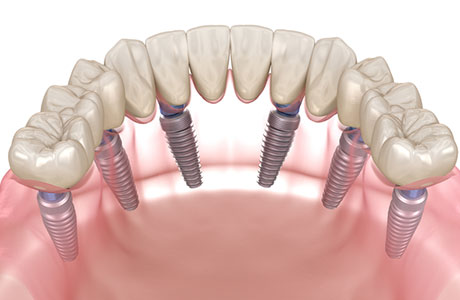

オールオン4

- オールオン4は、インプラントを顎の骨に固定して人工歯を支えるため、総入れ歯と比べて高い咬合力が期待できます。硬い食材も無理なく噛めるようになり、食事の満足度や日常の快適さが大きく向上します。

- 歯を失ったままにすると顎の骨は徐々に痩せていきますが、インプラントは噛む力を骨に伝えるため、骨吸収の抑制が期待できます。オールオン4は長期経過でも骨の安定が報告されており、将来を見据えた治療法として選ばれています。